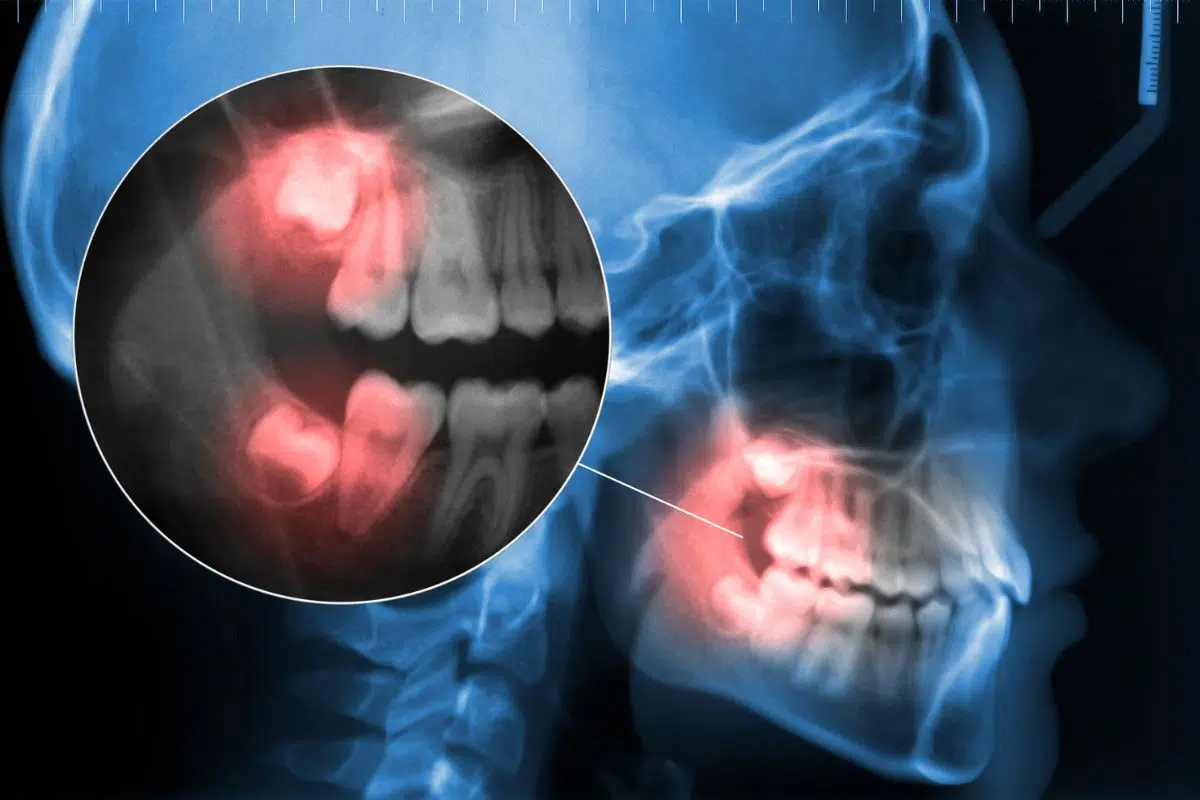

Impacted Wisdom Teeth

Sometimes, third molars become impacted, meaning they do not have enough space to emerge properly from the gums. If this happens, the tooth can shift, causing pain or further discomfort. In rare situations, the tooth may appear loose or fall out independently.